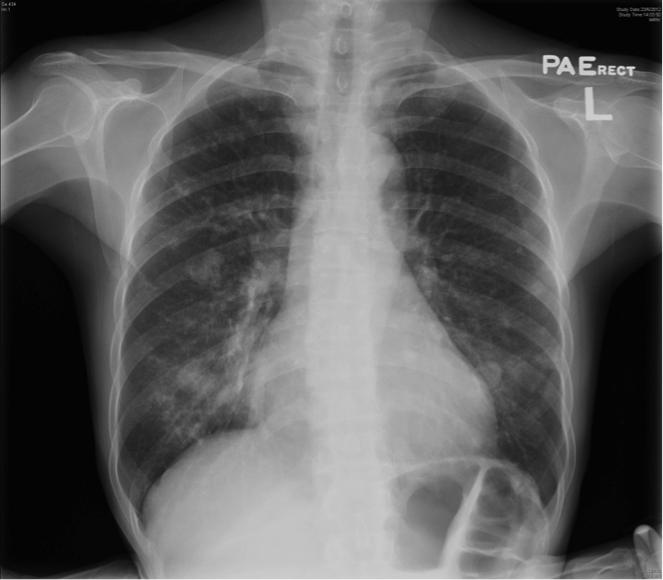

The patient was a chronic smoker (30 pack-years) and chronic drinker. He was a construction site worker and his past health was good. He presented with headache for a few weeks and was found to have signs of superior vena cava obstruction (SVCO). He did not have other complaint and the rest of the physical examination was normal. His CXR was unremarkable (Fig 4). His plain CT brain was also unremarkable. His initial blood tests including complete blood picture, renal & liver function test, erythrocyte sedimentation rate, urate, lactate dehydrogenase and tumor markers (including carcinoembryonic antigen, alpha-fetoprotein and prostate-specific antigen) were normal. His sputum was negative for culture, acid fast bacilli and cytology. His contrast CT thorax showed enlarged lymph nodes (LN) in the right lower paratracheal, pre-carinal & right hilar region and aorto-pulmonary window. The enlarged right lower paratracheal and precarinal LN compressed the brachiocephalic veins and superior vena cava (Fig 5). FOB with transbronchial needle aspiration under endobronchial ultrasound guidance (EBUS-TBNA) were done. The specimen of the right lower paratracheal LN was reported as suboptimal while the specimen from the right hilar LN was negative for any significant pathology. In view of SVCO was a potential medical emergency, we suggested surgical biopsy of the mediastinal LNs to ascertain their nature more definitively in order to guide subsequent management. He was then referred to the thoracic surgery clinic and PET-CT was done as suggested by the thoracic surgeon. The PET-CT was reported as “There were multiple enlarged hyper-metabolic mediastinal LNs (SUVmax 3.3-6.5) and the provisional diagnosis would include lymphoproliferative disease.” A hypermetabolic focus (1.7cm x 1.0cm x 2.3cm, SUVmax = 4.7) in the periphery of the right vastus lateralis muscle was also found incidentally (Fig 6A, 6B). At that juncture, the working diagnosis was SVCO due to possible lung carcinoma with LN metastases or lymphoma. The right thigh lesion could be part of the disease or something unrelated. Right anterior mediastinotomy and biopsy of the right lower paratracheal LN were done. Histology showed a piece of fibrous tissue with marked suppurative granulomatous inflammation. However, infective stains including Ziehl-Neelsen (ZN) stain were negative. His tuberculin skin test was 24mm (that was strongly positive) and his histoplasma antibody was negative. Standard anti-tuberculosis (TB) treatment was started and the signs of SVCO resolved progressively. Later, ultrasound guided FNA of his right thigh lesion showed granulomatous inflammation and one acid fast bacillus. Thus the final diagnosis was TB mediastinal lymphadenopathies causing SVCO, and right thigh TB infection. An interval CT about four months after anti-TB treatment showed the mediastinal LNs were decreased in size.

Figure 4